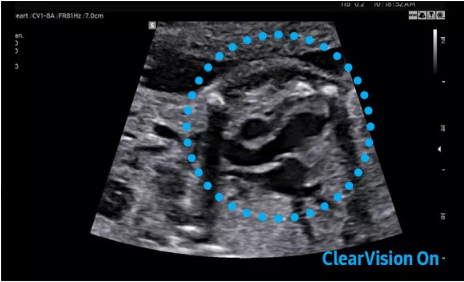

2D成像方面,Hera i10集成了包括ShadowHDR?、HQ-Vision?、ClearVision等多項(xiàng)具有三星“血統(tǒng)”的技術(shù),加強(qiáng)了圖像的陰影抑制、減少偽影、緩和模糊區(qū)。